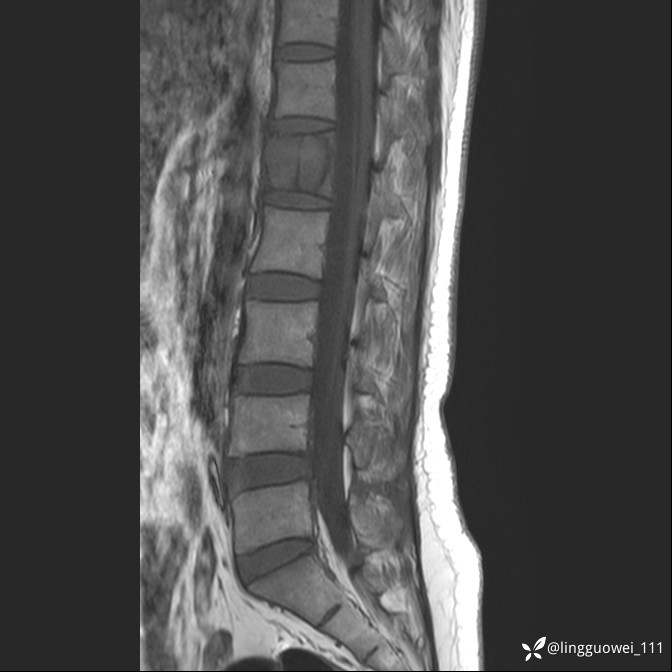

病例女,39岁,腰痛来诊,只有CT可能要鉴别诊断,而MR可以定性吗?

患者性别:女

患者年龄:39岁

主诉:腰痛

T1

T2

T2+FS

T1+C

DWI ADC